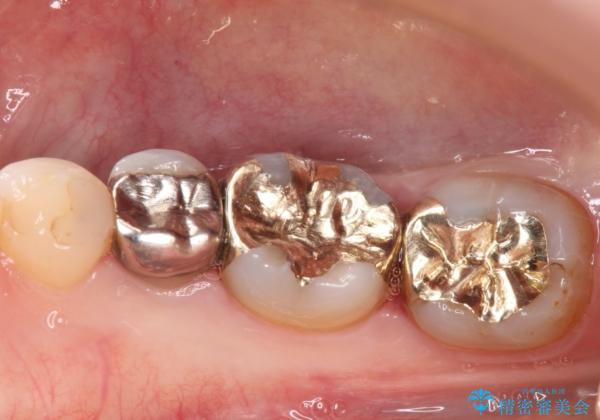

下の奥歯の虫歯をゴールドインレーで治療

- 奥歯の虫歯を心配して来院した患者様です。

レントゲン写真から、以前治療した詰め物の下に虫歯があることがわかりました。

精度が高く、虫歯の再発リスクの低いゴールドインレーで治療を行うこととしました。

ゴールドインレーは適合がよいため、虫歯の再発のリスクが少ない非常に優れた材料です。

ゴールドインレーはセラミックインレーと比べ、割れるリスクが低いため、咬合力が強い方にお勧めです。